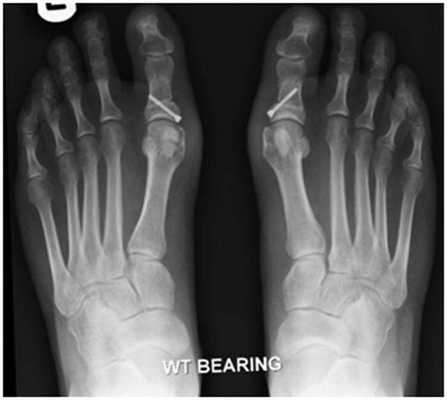

Фото до и после операции.

Операция продольно-поперечной деформации.